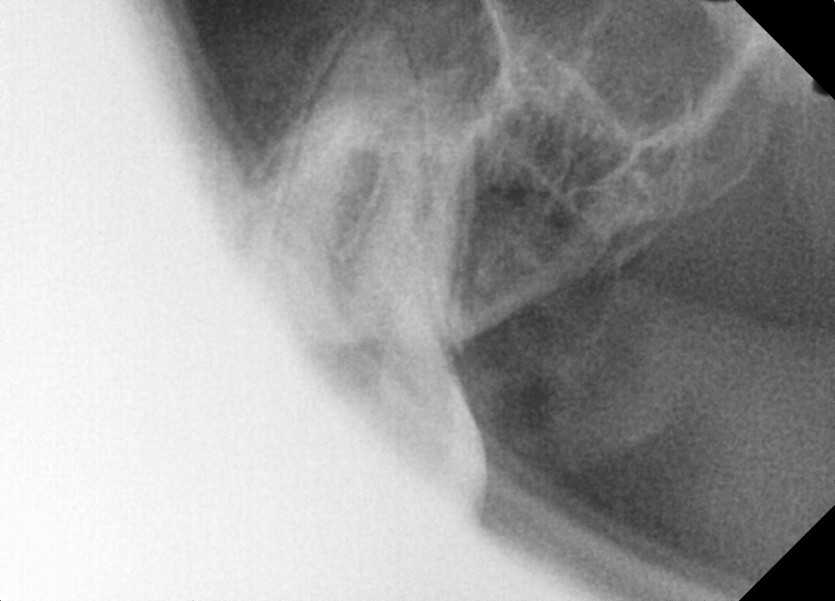

#28,38 사랑니 발치

구강 외과 전문의가 당일 발치하였습니다.